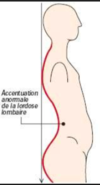

Décrire : Lordose

Concavité postérieur de la colonne vertébrale